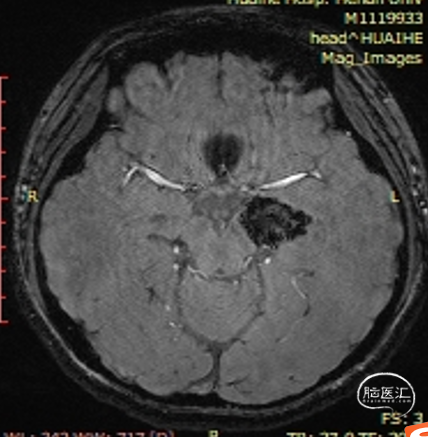

术前影像:

左侧海马旁回海绵状血管瘤。